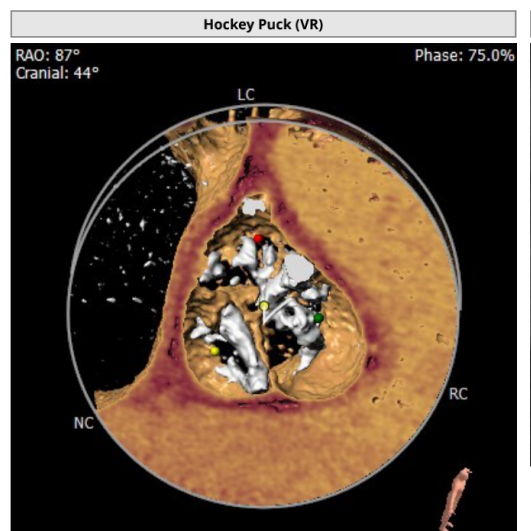

CT评估

钙化积分及分布

入路情况

难点分析

该患者为二叶式畸形主动脉瓣极重度钙化,钙化积分高达1333,且在左右冠窦交界处存在钙化粘连,瓣膜下滑风险增加,球扩时瓣环撕裂风险增加;

心脏角度略大,输送器跨瓣困难,释放瓣膜时,瓣膜与瓣环同轴性差;

因患者为二叶式主动脉瓣畸形,左右冠窦交界处容易发生瓣周漏。